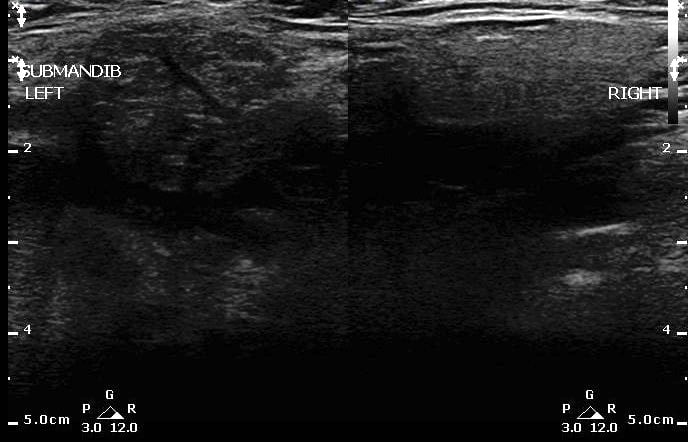

- Comparison of Sialadenitis on the left and normal submandibular gland on right:

- Figure 21. Sialadenitis (left) vs normal (right)